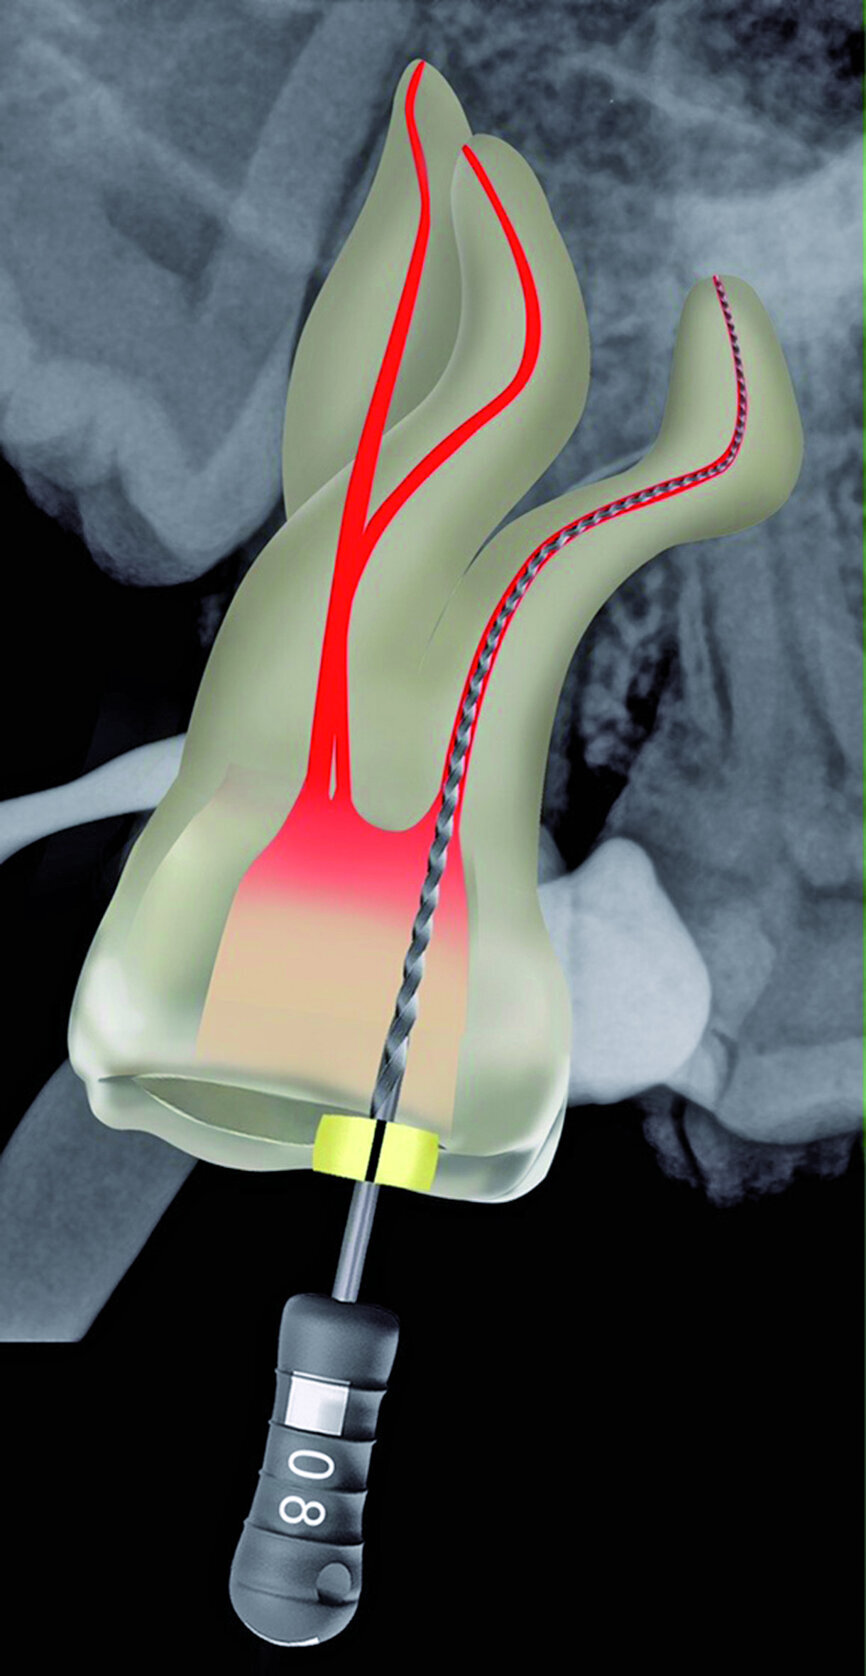

Fig. 25: A WaveOne Gold Glider was used in a reciprocating motion to further expand the glide paths in the two buccal root canals.

The pulp chamber was filled with Glyde (Dentsply Sirona) before the canals were carefully negotiated to full working using pre-curved size 08 K-Files (Fig. 19). Working length measurements obtained from an electronic apex locator reading corresponded with the lengths obtained from the 3D Endo Software. These measurements were also confirmed radiographically (Fig. 20). A reproducible glide path was prepared in each root canal system with the size 08 K-File in an M4 Reciprocating handpiece (Sybron Endo; Fig. 21), followed by making a size 10 K-File ‘super loose’ (Fig. 22). A ProGlider (Dentsply Sirona) was used in a rotary motion to expand the glide path in the palatal root canal (Fig. 23). Considering the sharp and severe curvatures in the two buccal canals, it was decided to convert the ProGlider instrument into a manual file to expand the glide path in these tortuous canals with more safety (Fig. 24). The manually adapted ProGlider was used in a balanced force motion up to working length. In addition, to create more safety during the canal preparation of the two challenging buccal root canals, it was also decided to use the reciprocating WaveOne Gold Glider (Dentsply Sirona; Fig. 25), after the ProGlider instrument to further expand the glide paths. The WaveOne Gold Glider was used in 4–8 backstroke brushing motions from working length, in the two buccal root canal systems.

The ProGlider, a single file rotary glide path instrument was the first instrument used to expand the glide paths. This file is manufactured from M-wire NiTi alloy that shows more flexibility and resistance to cyclic fatigue compared to conventional NiTi alloy. It has a semi-active tip, size ISO 016 (D0) with a 2 % taper that progressively increases up to 8 % (D14; Fig. 29). The cross section of the ProGlider instrument is square and the file is used in a continuous rotary motion at 300 rpm and a torque setting of 2–4 Ncm. [14] Considering the severe curvatures in different planes of the buccal root canal systems, the ProGlider instrument was first used in a manual mode up to working length in these two canals. It was also then decided to further expand the glide path in these canals by using the WaveOne Gold Glider, also a single, reciprocating glide path file designed for glide path enlargement. Here, a second glide path instrument was used because the cutting envelope of the WaveOne Gold Glider is more than the ProGlider instrument (Fig. 30). The rationale for this double file approach for glide path expansion was to enhance safety for the preparation files that followed.

The file tip of the WaveOne Gold Glider at D0 has a ISO 015 tip size with a 2 % taper, and the taper progressively increases up to 6 % (D16; Fig. 29). The file has a semi-active tip and a parallelogram-shaped cross-section. The WaveOne Gold Glider is manufactured using NiTi wire subjected to a post-manufacturing thermal process, whereby a new phase-transition point between martensite and austenite is identified to produce a file with super-elastic NiTi metal properties. [15] This process gives the file a gold finish with enhanced flexibility and resistance to cyclic fatigue compared to conventional NiTi and M-wire alloys. The WaveOne Gold Glider was driven by the X-Smart motor, on the WaveOne setting. The file was taken up to working length in the already secured and expanded glide path and the glide path was further expanded by using a 4–8 backstroke brushing motions, until the file felt completely loose in the challenging canal systems.